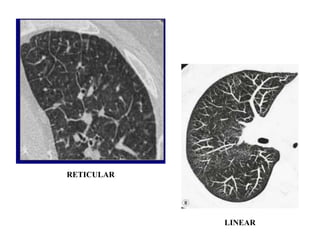

RETICULAR/LINEAR PATTERN:-

• TOO MANY LINES EITHER AS ARESULT OF

THICKENING OF LUNG INTERLOBULAR

SEPTA OR INTRALOBULAR SEPTA.

• THICKENING OF LUNG INTERSTITIUM BY

FLUID ,FIBROUS TISSUE OR INFILTRATION BY

CELLS RESULTS IN PATTERN OF RETICULAR

OPACITY DUE TO THICKENING OF SEPTA.

Linear opacities can develop:

• When the interstitium is thickened

• When lymphatics are involved

• When peripheral acinar alveoli are

filled or collapsed

• When blood vessels and airways are

involved

• When lung atelectasis or fibrosis occurs

RETICULAR

LINEAR